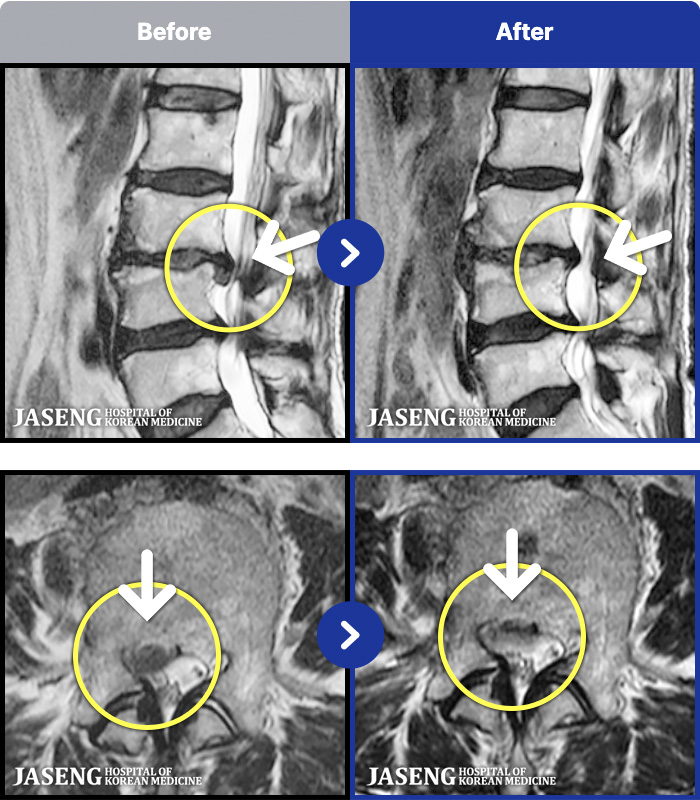

1,286 MRI ũ ʸ Ȯϼ.

ȯںп Ǹ ǿ ԿǾ, ο ġ ۿ Ƿ ġḦ Ͻñ ٶϴ.